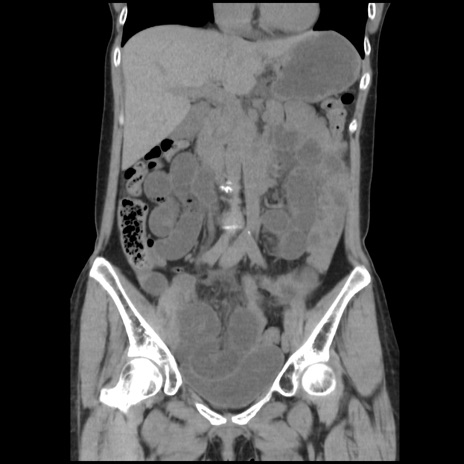

症例32(冠状断像)

【症例】40歳代 女性

【主訴】上腹部痛、嘔気・嘔吐

【現病歴】約9時間前頃から急に上腹部痛、嘔気、嘔吐が出現。改善しないため救急要請。

【既往歴】子宮頚癌(広汎子宮全摘術、放射線療法)、腸閉塞

【身体所見】腹部:平坦、軟、腸雑音亢進、上腹部を中心に腹部全体に圧痛あり。

【データ】WBC 8400、CRP 0.03